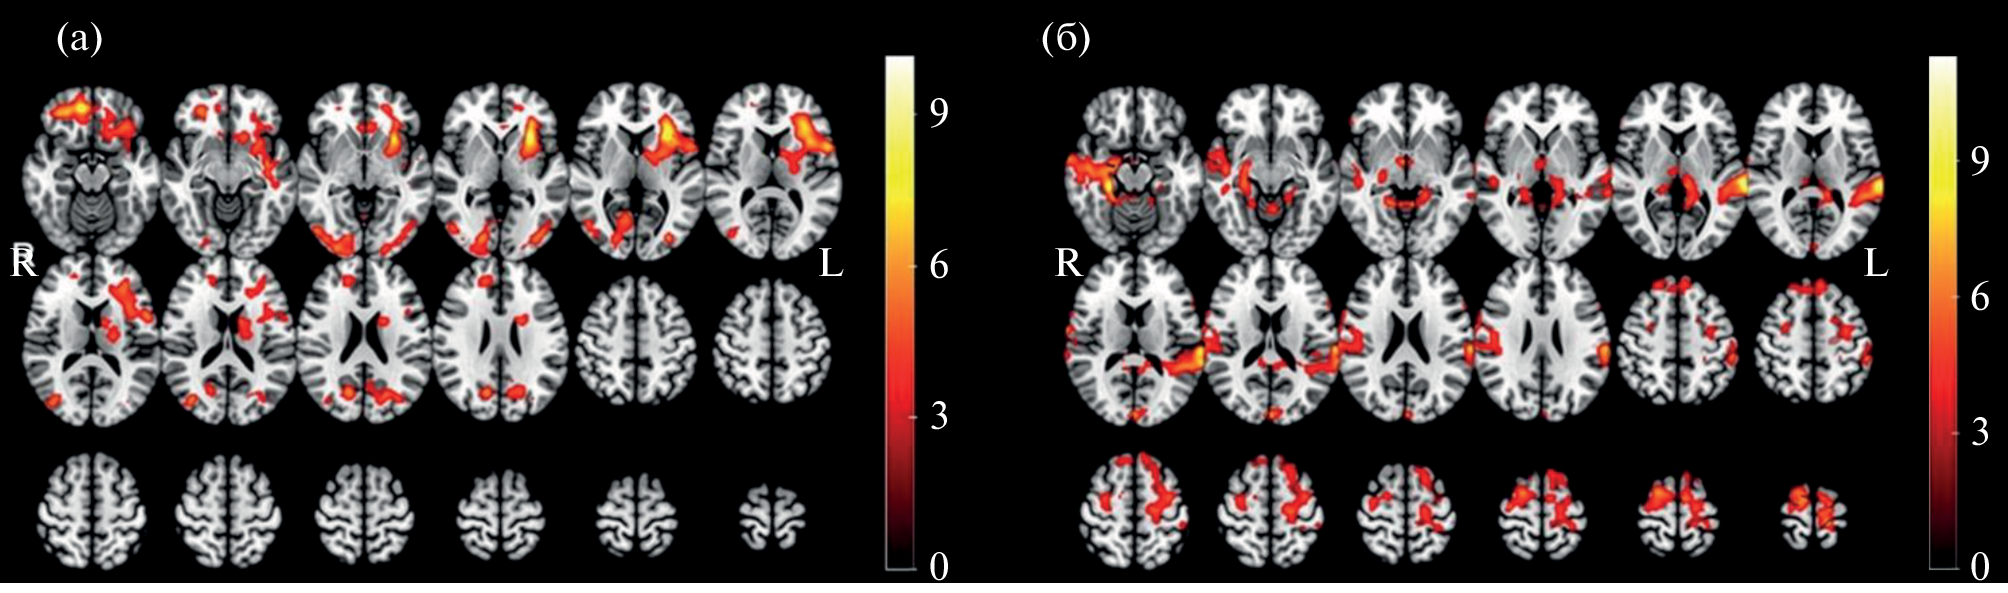

A group of 20 healthy subjects (11 males and 9 females) performed a selective auditory attention task in a dichotic listening paradigm with different levels of perceptual load. Analysis of brain activation patterns measured with fMRI during selective listening to fusion speech with distractors of varying strengths revealed statistically significant sex differences in the topography of cortical activity. “Female > male” effects dominated in the left superior temporal gyrus and the left pre and postcentral gyrus; while the most pronounced “male > female” effects were found in the left islet, shell and frontal lobule. Statistically significant effects were also obtained by comparing activation patterns according to the level of task complexity: It was shown that masking with a female speaker’s voice caused greater activation of additional high-level information processing areas. The findings indicate the presence of sexual dimorphism in the organization of the selective auditory attention system.